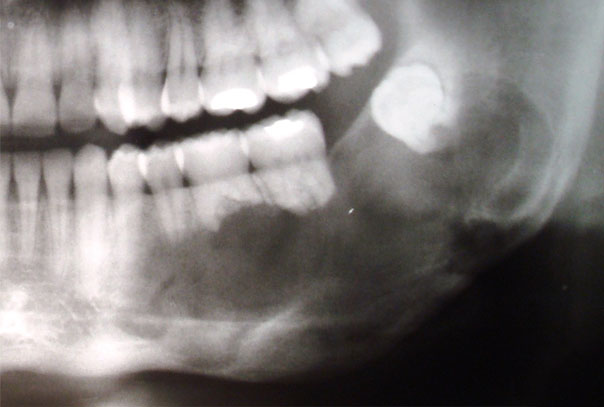

ContáctenosQuistes y tumores maxilares

Los quistes y tumores a nivel de los maxilares son una alteración relativamente frecuente. Solo en casos poco frecuentes, estos ya sea por el tamaño o por su etiología pueden generar secuelas más graves como pérdida de dientes, de tejido óseo o incluso invadir estructuras vecinas.

En la mayoría de ocasiones los quistes tienen un origen dental. Se produce a consecuencia de la extensión de la infección que afecta el diente y al hueso que rodea éste.

Nuestro objetivo es realizar la exéresis del quiste o tumor, en la mayoría de los casos de forma conservadora, y reconstruir las regiones afectadas para que no exista ninguna secuela.

El cirujano valorará cada caso individualmente, con especial atención al origen de la lesión, y a la extensión y afectación de estructuras vecinas. Para ello, habitualmente se requiere de la realización de una TAC que nos aporta una información detallada.

La exéresis del quiste requiere en cada caso tratamientos diferentes dependiendo del estado del diente, de la endodoncia, del tamaño del quiste, de su origen, de la afectación de dientes vecinos, etc.

El tratamiento de estas patologías consistente en la extracción de la lesión que se realiza con anestesia general o local, totalmente indoloro, y con un postoperatorio que cursa con algo de edema, molestias ligeras, y que requiere de una dieta blanda durante unos días. El procedimiento quirúrgico puede requerir además la reconstrucción mediante hueso heterólogo (hueso artificial) o autólogo del resto del maxilar y la reconstrucción de encía y partes blandas para obtener una buena salud periodontal y una buena estética.

Sin embargo, en patologías de gran tamaño, o de origen no dental, el tratamiento de estos requiere intervenciones mucho más avanzadas, con ingreso hospitalario.